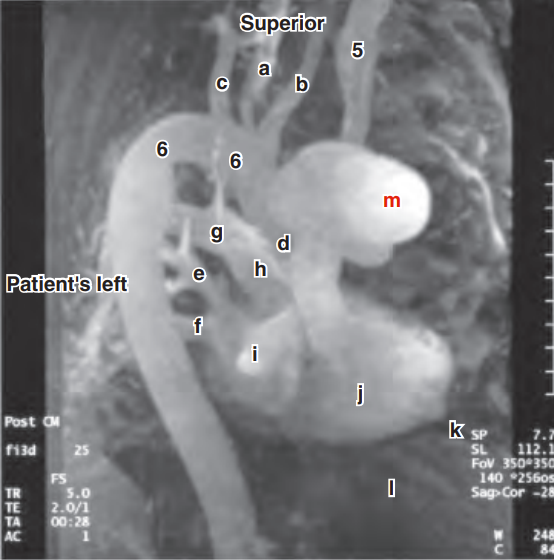

Label the parts of the duodenum

A & B - superior

C - descending

D - horizontal

E - ascending

What are the two flexures of the duodenum?

Superior and inferior duodenum

What is the peritoneal relationship of the duodenum?

Retroperitoneal (except first 1 - 2cm)

L1 to L3